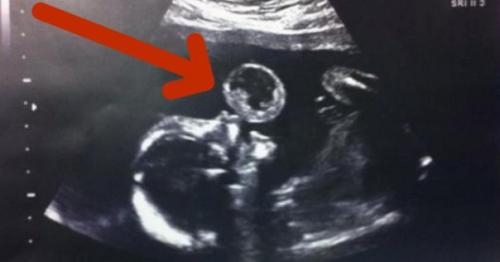

На узи видно, как малыш надувает пузырь.

Тамми гонзалес из США была на 17 неделе беременности, когда врачи обнаружили нечто необычное вовремя очередного сеанса узи. Казалось, будто малыш в утробе надувает пузырь. Увиденное, как бы там ни было, оказалось тератомой, редкой разновидностью раковой опухоли. Врачи рекомендовали тамми немедленно провести операцию по удалению образования, пока малыш еще находится в утробе. Иначе девушка могла потерять ребенка.